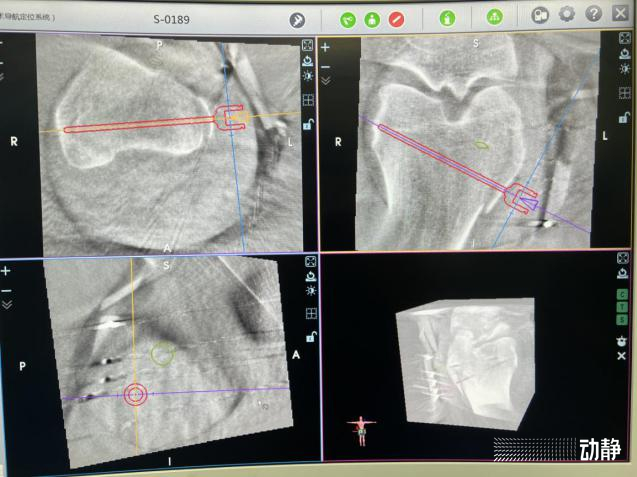

经过严密的诊疗和反复论证,创伤治疗团队决定采用骨科机器人进行手术,不仅切口小,而且一次性多次置钉,节省时间,减少创伤,可以让患者得到最佳的治疗效果。